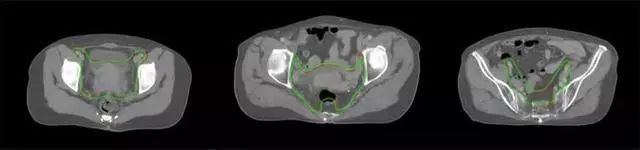

四、放射治療智能勾畫(huà)軟件

放射治療,簡(jiǎn)稱(chēng)放療,是治療腫瘤主要手段之一,利用放射線(xiàn)破壞照射區(qū)(靶區(qū))的細(xì)胞,使腫瘤細(xì)胞停止分裂直至死亡,醫(yī)生通常把放射治療形象的比喻為“打靶”,放療前精準(zhǔn)勾畫(huà)腫瘤靶區(qū)范圍是腫瘤放射治療的關(guān)鍵步驟。傳統(tǒng)的靶區(qū)勾畫(huà)醫(yī)生會(huì)根據(jù)患者多張CT、MRI影像片憑借經(jīng)驗(yàn)進(jìn)行,比較耗時(shí),治療的病人數(shù)量也有限,且靶區(qū)勾畫(huà)缺少行業(yè)統(tǒng)一的規(guī)范和標(biāo)準(zhǔn),無(wú)法達(dá)到同質(zhì)化,勾畫(huà)精確度不理想。

技術(shù)原理

基于深度學(xué)習(xí)人工智能的放療靶區(qū)智能勾畫(huà)技術(shù)和自動(dòng)計(jì)劃技術(shù),基于全面的市場(chǎng)調(diào)研和臨床專(zhuān)業(yè)意見(jiàn),采用獨(dú)創(chuàng)的基于小樣本量的人工智能算法,實(shí)現(xiàn)放療靶區(qū)和危及器官的快速全自動(dòng)勾畫(huà)。

產(chǎn)品優(yōu)勢(shì)

縮短至幾分鐘內(nèi)便可完成,大幅提升了放療效率,且人工智能平臺(tái)完成的靶區(qū)勾畫(huà)可基本滿(mǎn)足臨床醫(yī)生需求,專(zhuān)家只需審核時(shí)細(xì)微調(diào)整,可顯著提高靶區(qū)勾畫(huà)的規(guī)范化及精準(zhǔn)度,讓放療智能化,標(biāo)準(zhǔn)化??筛采w食管癌、鼻咽癌、直腸癌、宮頸癌、肺癌等多種病種。